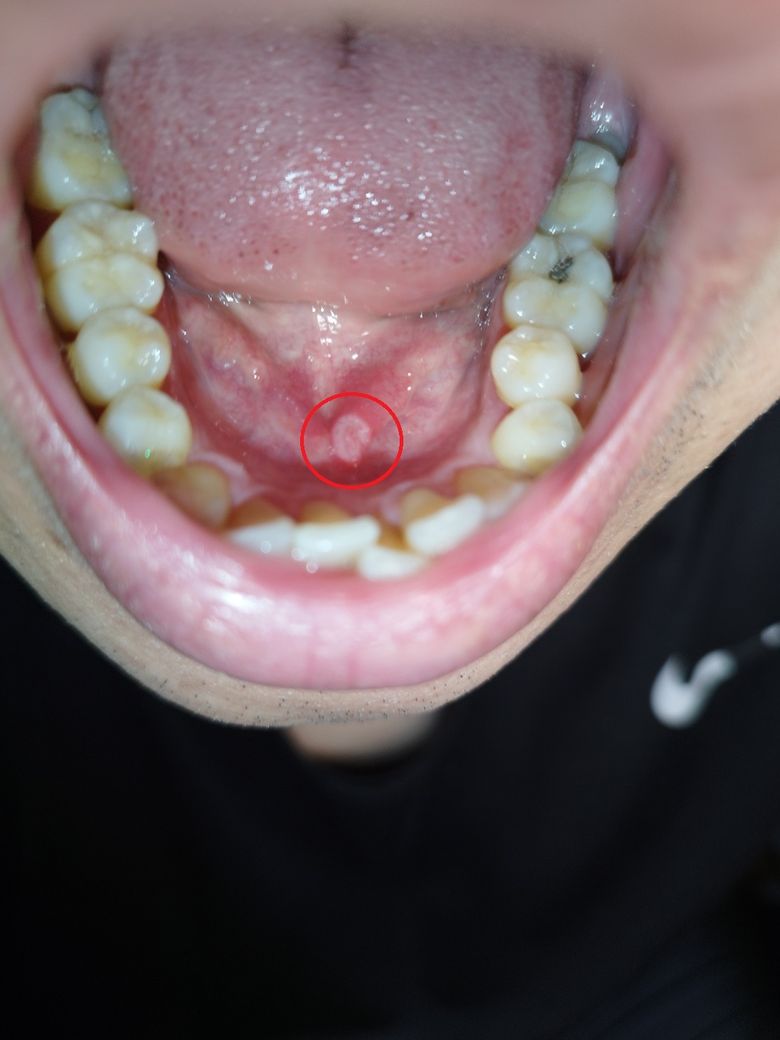

입에 구내염같은 하얀 염증? 포진? 같은게 생겼는데 안아파요

입에 구내염같은 하얀 염증? 포진? 같은게 생겼는데 전혀 안아파요

안아파서 더 불안하네요ㅠㅠ 어떤 증상인걸까요? 사진첨부합니다.

• 1번 째 사진

사진상 모양만 보았을때 제 개인적인 소견은 "oral homogenous leukoplakia"로 의심이 됩니다.

가까운 치과대학병원 구강악안면외과를 찾아가셔서 조직검사를 받길 권유드립니다.

현재 사진상으로 구내염증상으로 보이며, 통증이 없는 경우 거의 나아가는 단계일 가능성이 높습니다. 만약 통증이 있거나 커지는 경우에는 치과를 방문하길 권합니다.